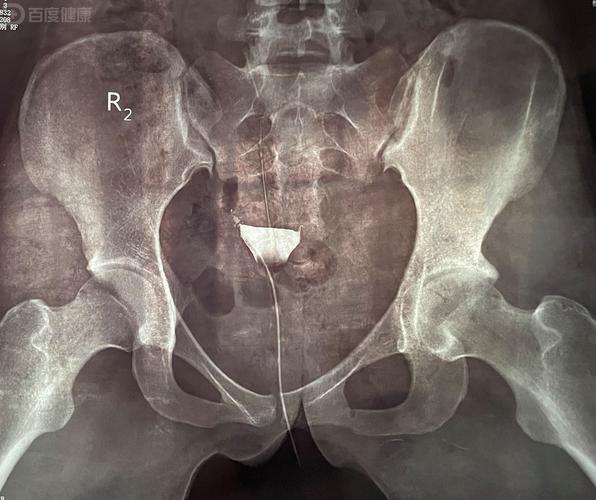

- 强烈建议避免在月经可能受孕的时期(即排卵期前后)进行X光检查,尤其是盆腔部位的检查。

- 如果已经确认怀孕,绝对禁止进行X光检查,尤其是腹部和盆腔的检查。

- 靠近或涉及盆腔和腹部(如腰椎、消化道造影、静脉肾盂造影):这些检查的风险相对较高,如果检查发生在排卵期前后,建议咨询医生,医生可能会建议您等待一个完整的月经周期后再开始备孕,以确保体内没有受精卵,这主要是作为一种预防性的“安全等待”。